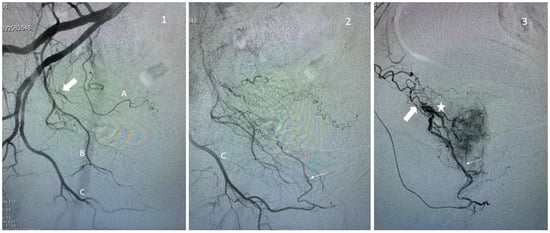

When no prostatic artery is found in the territory of the internal iliac, one should always consider looking for a possible origin from the external iliac via an accessory obturator artery (1.8% of patients [7]) or via the epigastric artery (the so-called “corona mortis artery”). Additionally, in the cases of occlusion of the prostatic artery and, in particular, of the central artery, the flow is usually supplied by collaterality, by a frequency in the distality of the internal pudendal artery (Figure 3), the peripheral or contralateral prostatic artery, and the obturator artery.

Figure 3.

Examples of prostate artery occlusion and revascularization of the prostate via a distal pudendal/prostatic apical shunt. Image 1: Internal iliac angiography demonstrating a vesical inferior artery (A), an obturator artery (B), and an internal pudendal artery (C). Note the occluded prostatic artery (arrow). Image 2: Supraselective angiography of the internal pudendal artery (C) showing a connexion with the prostatic artery via an apical shunt (thin arrow). Image 3: Retrograde catheterism of the prostatic artery (thin arrow) and opacification demonstrating opacification of the prostatic central branch (star) and confirming occlusion of a proximal prostatic artery (large arrow).